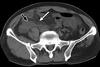

16

Abdome: cólon e reto

A maioria dos pacientes com diverticulose tem doença no cólon ______(direito/esquerdo), porém a do cólon _______(direito/esquerdo) é frequente em pacientes asiáticos (43%-50%).

A

Esquerdo; direito.

Diverticulose cólica (seta reta). Hipertrofia da camada muscular (seta curva)